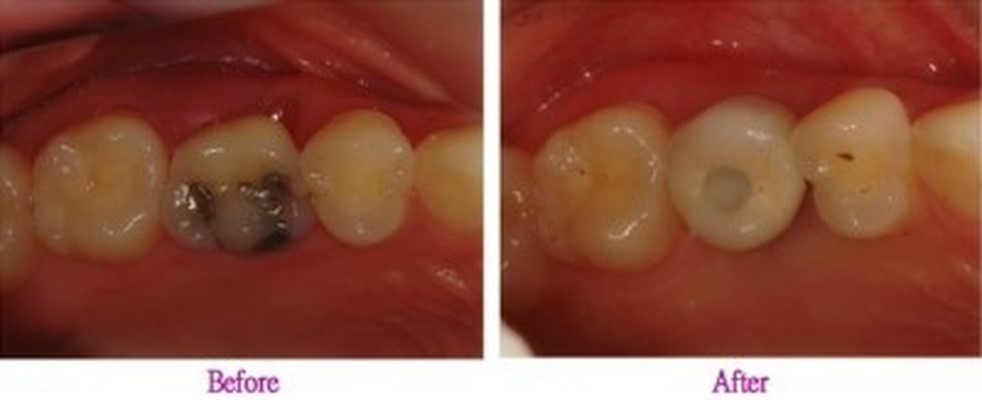

치아의 정상적인 교합은 저작 능력을 높이며 치아의 불필요한 마찰을 줄여 치아가 갈리거나 수명이 줄어드는 것을 방지할 수 있습니다.

▶ 상악과 하악의 명확한 교합을 위해 적정한 각도로 임플란트를 식립하여 정교하고 강도 높은 보철 제작으로 실제 사용 시 불편함을 제거합니다.

음식을 씹을 때 흔들리거나 이물감이 들지 않도록 임플란트가 뼈와 강하게 결합되는 것이 중요한데요. 이는 임플란트의 수명과 직결되는 요소로 친수성이 높은 칼슘 임플란트를 사용하여 임플란트와 치조골간 골 생성이 치밀하고 우수하여 강한 골 결합력을 유지하도록 해야 합니다.